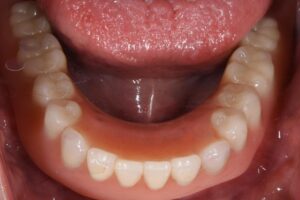

【初診時の下顎のお口の写真】

2本、歯が残ってはいるが、かなり厳しい状態・・・